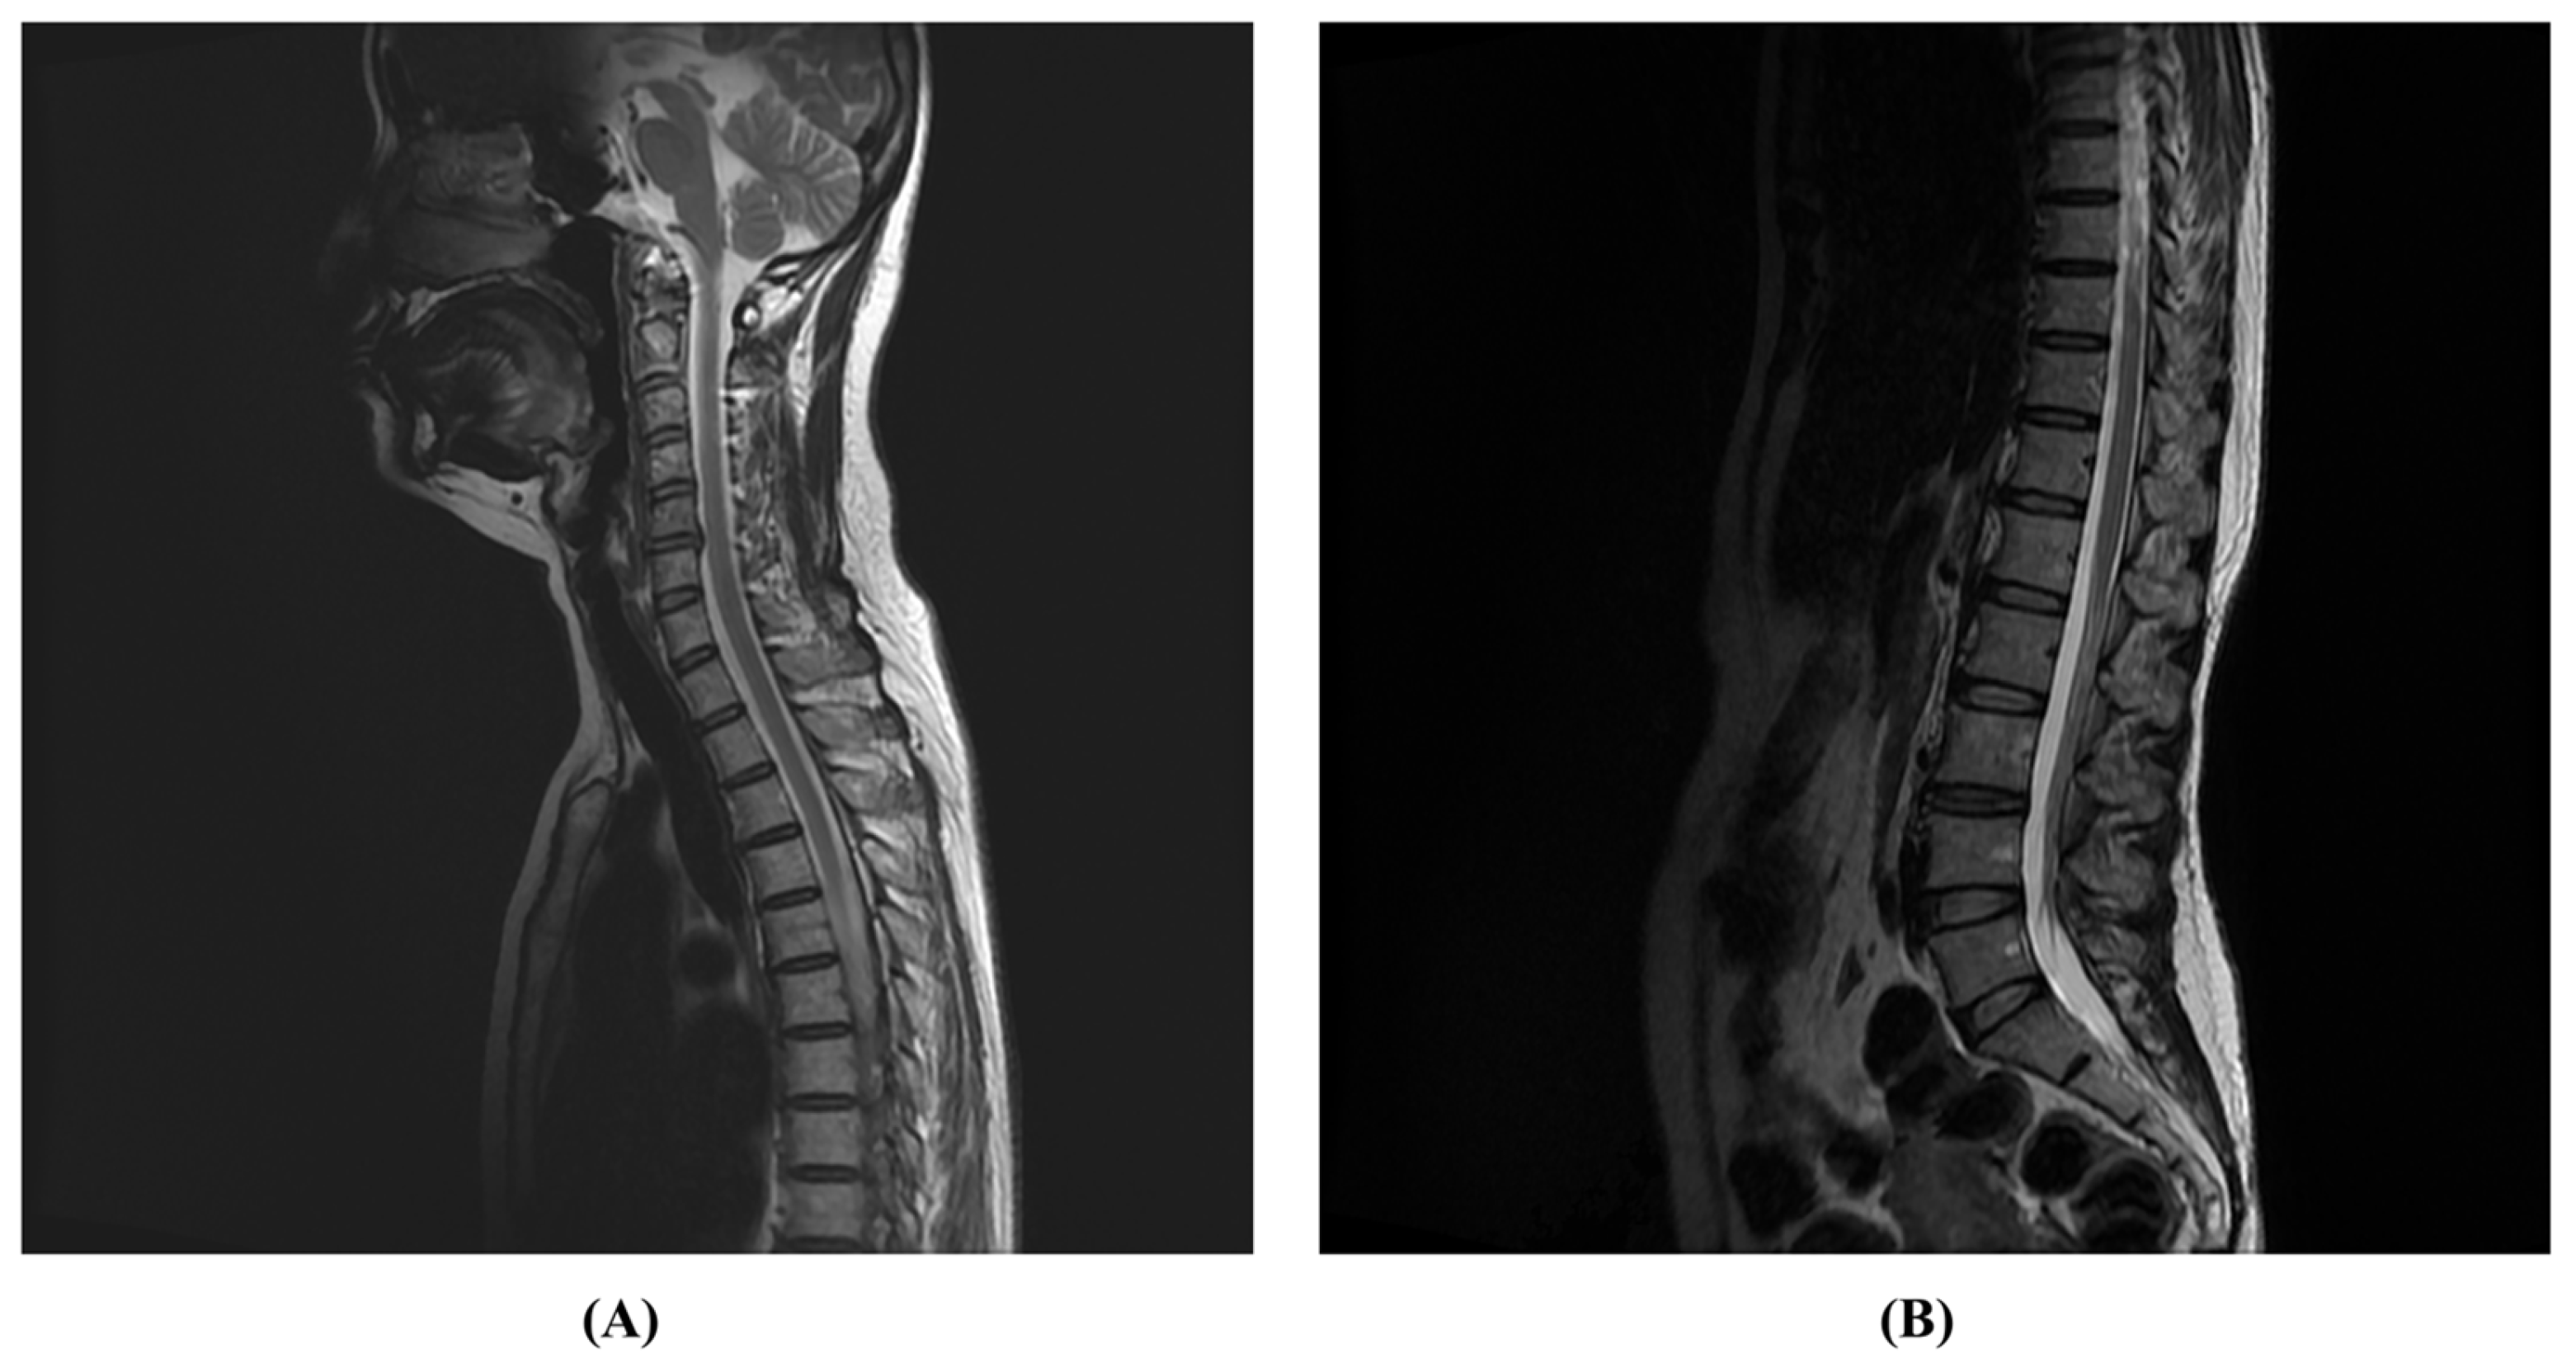

2. Case Presentation